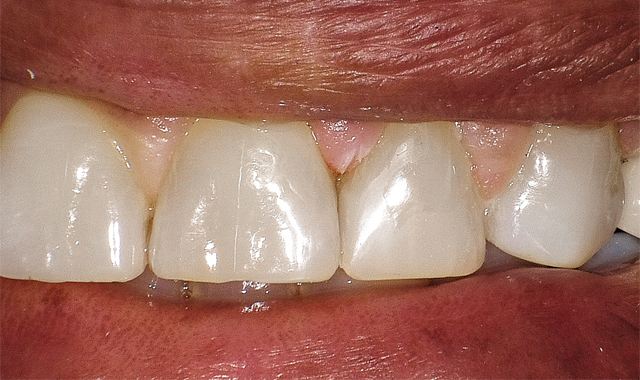

This case involved replacing a chipped Class IV on number 10 (Fig. 4).

Case 2 involved replacing a chipped Class IV on No. 10.

The beauty of the G-ænial Sculpt system is that one can get a superior chameleon effect from using a core shade (A2, for example) but in the case presented, we simply layered an A2O, then an A1 and then AE (adult enamel) over the very outer layer.

Fig. 7 shows the chameleon effect of G-ænial Sculpt. The great results led to congratulations going out to GC America in receiving The Catapult Vote of Confidence for G-ænialTM Sculpt.

The chameleon effect of G-aenial Sculpt is illustrated here.